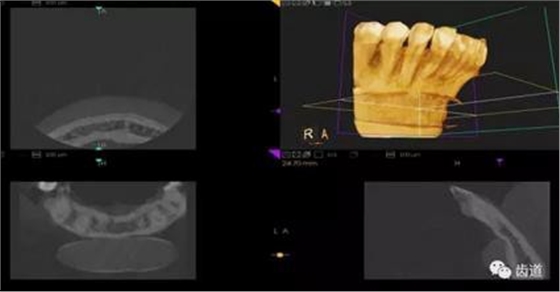

三)種植修復(fù)

CBCT在牙種植修復(fù)中的應(yīng)用。種植前利用CBCT對患者的牙床進(jìn)行檢查,可精準(zhǔn)判斷牙槽骨的寬度、厚度及高度、骨的密度、重要的顏面神經(jīng)、血管和鼻竇位置等。臨床醫(yī)生不僅可以在計(jì)算機(jī)直觀的看到牙槽骨的立體影像,還可以切換不同的視角來觀察硬組織之間的位置關(guān)系,在手術(shù)方案中避開危險(xiǎn)區(qū)域,保證手術(shù)的安全性。臨床醫(yī)生還可以利用CT數(shù)據(jù)進(jìn)行數(shù)字模型重建,配合軟件預(yù)先做好手術(shù)模板,使種植手術(shù)更安全快捷,避免在種植手術(shù)過程中不慎破壞神經(jīng)、鼻竇等解剖結(jié)構(gòu),導(dǎo)致顏面神經(jīng)麻痹、鼻竇炎等并發(fā)癥的發(fā)生。

1、下頜骨種植牙前測量準(zhǔn)備影像

2、上頜骨種植牙前準(zhǔn)備影像